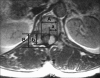

Methods: The spinal IDEM tumor patients (11 cases) who had been treated by surgical excision and who were followed up more than 1 year were retrospectively analyzed. Pain was evaluated by the visual analogue scale (VAS) and the neurologic function was assessed by Nurick's grade. The pathological diagnosis, the preoperative symptom duration, the tumor location on the sagittal and axial planes and the percentage of tumor occupying the intradural space were investigated. In addition, all these factors were analyzed in relation to the degree of the preoperative symptoms and the prognosis. On the last follow-up, the MRI was checked to evaluate whether or not the tumor had recurred.

Results: The most common diagnosis was schwannomas (73%), followed by meningiomas (18%). The percentage of tumor occupying the intradural space was 82.9 +/- 9.4%. The VAS score was reduced in all cases from 8.0 +/- 1.2 to 1.2 +/- 0.8 (p = 0.003) and the Nurick's grade was improved in all cases from 3.0 +/- 1.3 to 1.0 +/- 0.0 (p = 0.005). The preoperative symptoms were correlated with only the percentage of tumor occupying the intradural space (VAS; r(2) = 0.75, p = 0.010, Nurick's grade; r(2) = 0.69, p = 0.019). One case of schwannoma recurred.